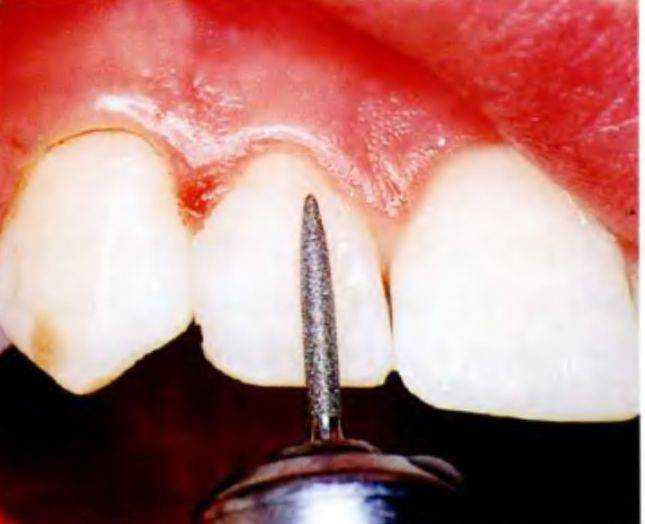

Зубы тщательно осушили струей воздуха и отвели щеки с помощью ретрактора для лучшей визуализации (рис. 6-12f). Цвет зубов определили с помощью цветовой шкалы. В большинстве случаев достаточно использования одного цвета для основной части зуба и одного цвета для пришеечной его части. У столь юной пациентки можно было ограничиться одним цветом.

Стоматолог всегда должен сидеть позади пациента, который находится в положении лежа. Ширину зубов измерили с помощью небольшой линейки и распределили имеющиеся пространства. Работу следует начинать с изменения формы центральных резцов.

Матрице придали необходимую форму для создания проксимальной поверхности зуба и сепарации зубов (рис. с 6-12g по 6-121). Матрицу адаптировали к зубу и нанесли композит (рис. 6-12j). Для нанесения

Центральным резцам придали необходимую форму (рис. 6-12р). Композит полимеризовали светом послойно (по 20 с на каждый слой) во избежание деформации подлежащих слоев при наложении следующих. Далее поверхность сгладили с помощью кисточки, затем приступили к боковым резцам (рис. 6-12q и 6-12г). После завершения нанесения компо-.